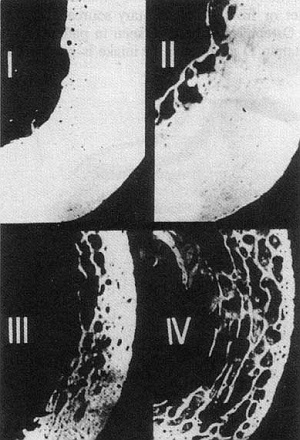

Четыре стадии остеопороза трабекулярной кости

Остеопороз возникает из-за дисбаланса в объеме активности остеокластов и остеобластов. Из-за потери гормональной стимуляции остеобластов восстановительные процессы замедляются до такого уровня, что в некоторых случаях может теряться почти 3% костной ткани в год. Этот процесс в большей степени локализован в губчатых, а не в монолитных костях. Кости в течение 5 – 10 лет теряют прочность настолько, что возникает риск переломов. Чаще всего переломы происходят в тех костях, которые испытывают максимальные нагрузки и напряжения при нормальной активности человека. Это кости таза и бедер, коленные суставы, берцовая кость, позвонки, запястье и плечевой сустав. Особенно тяжелым по последствиям считается перелом шейки бедра, ведущий к инвалидности и высокой (до 20%) смертности.